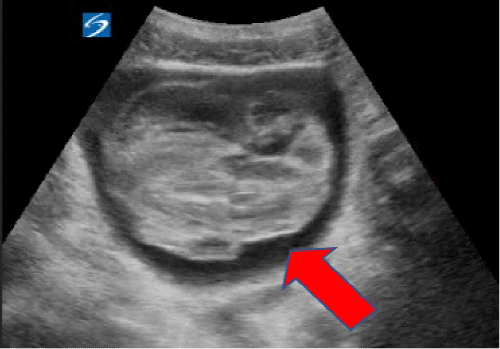

Upon arrival, the primary survey showed normal vital signs and a Glasgow Coma Scale (GCS) of 15. A secondary survey revealed tenderness in the right hemiabdomen and flank, but the abdomen was soft without signs of generalized peritonitis. A Focused Assessment of Sonography for Trauma (FAST) performed in the trauma bay detected fluid in the right upper quadrant and a significant amount of blood clots in the bladder (Figure 2). Initial lab tests showed a hemoglobin level of 13.4 g/dL, elevated white blood cell count (33,400), slightly elevated creatinine (1.20 mg/dL), and elevated liver enzymes (AST: 662 U/L, ALT: 397 U/L).

Figure 2. Focused Assessment with Sonography for Trauma (FAST) Images. Published with Permission

A) Significant clot burden within the bladder

B) Fluid collection in the right upper quadrant